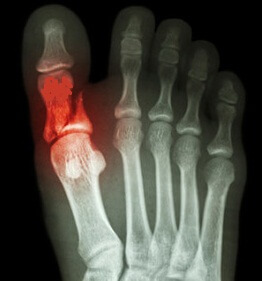

Диагностика

Основной метод выявления перелома пальца на ноге – проведение рентгенографического обследования. Зачастую изображения делают в двух проекциях. Это позволяет специалисту оценить масштабы поражения, выявить место разлома, наличие смещений отломков и пр.